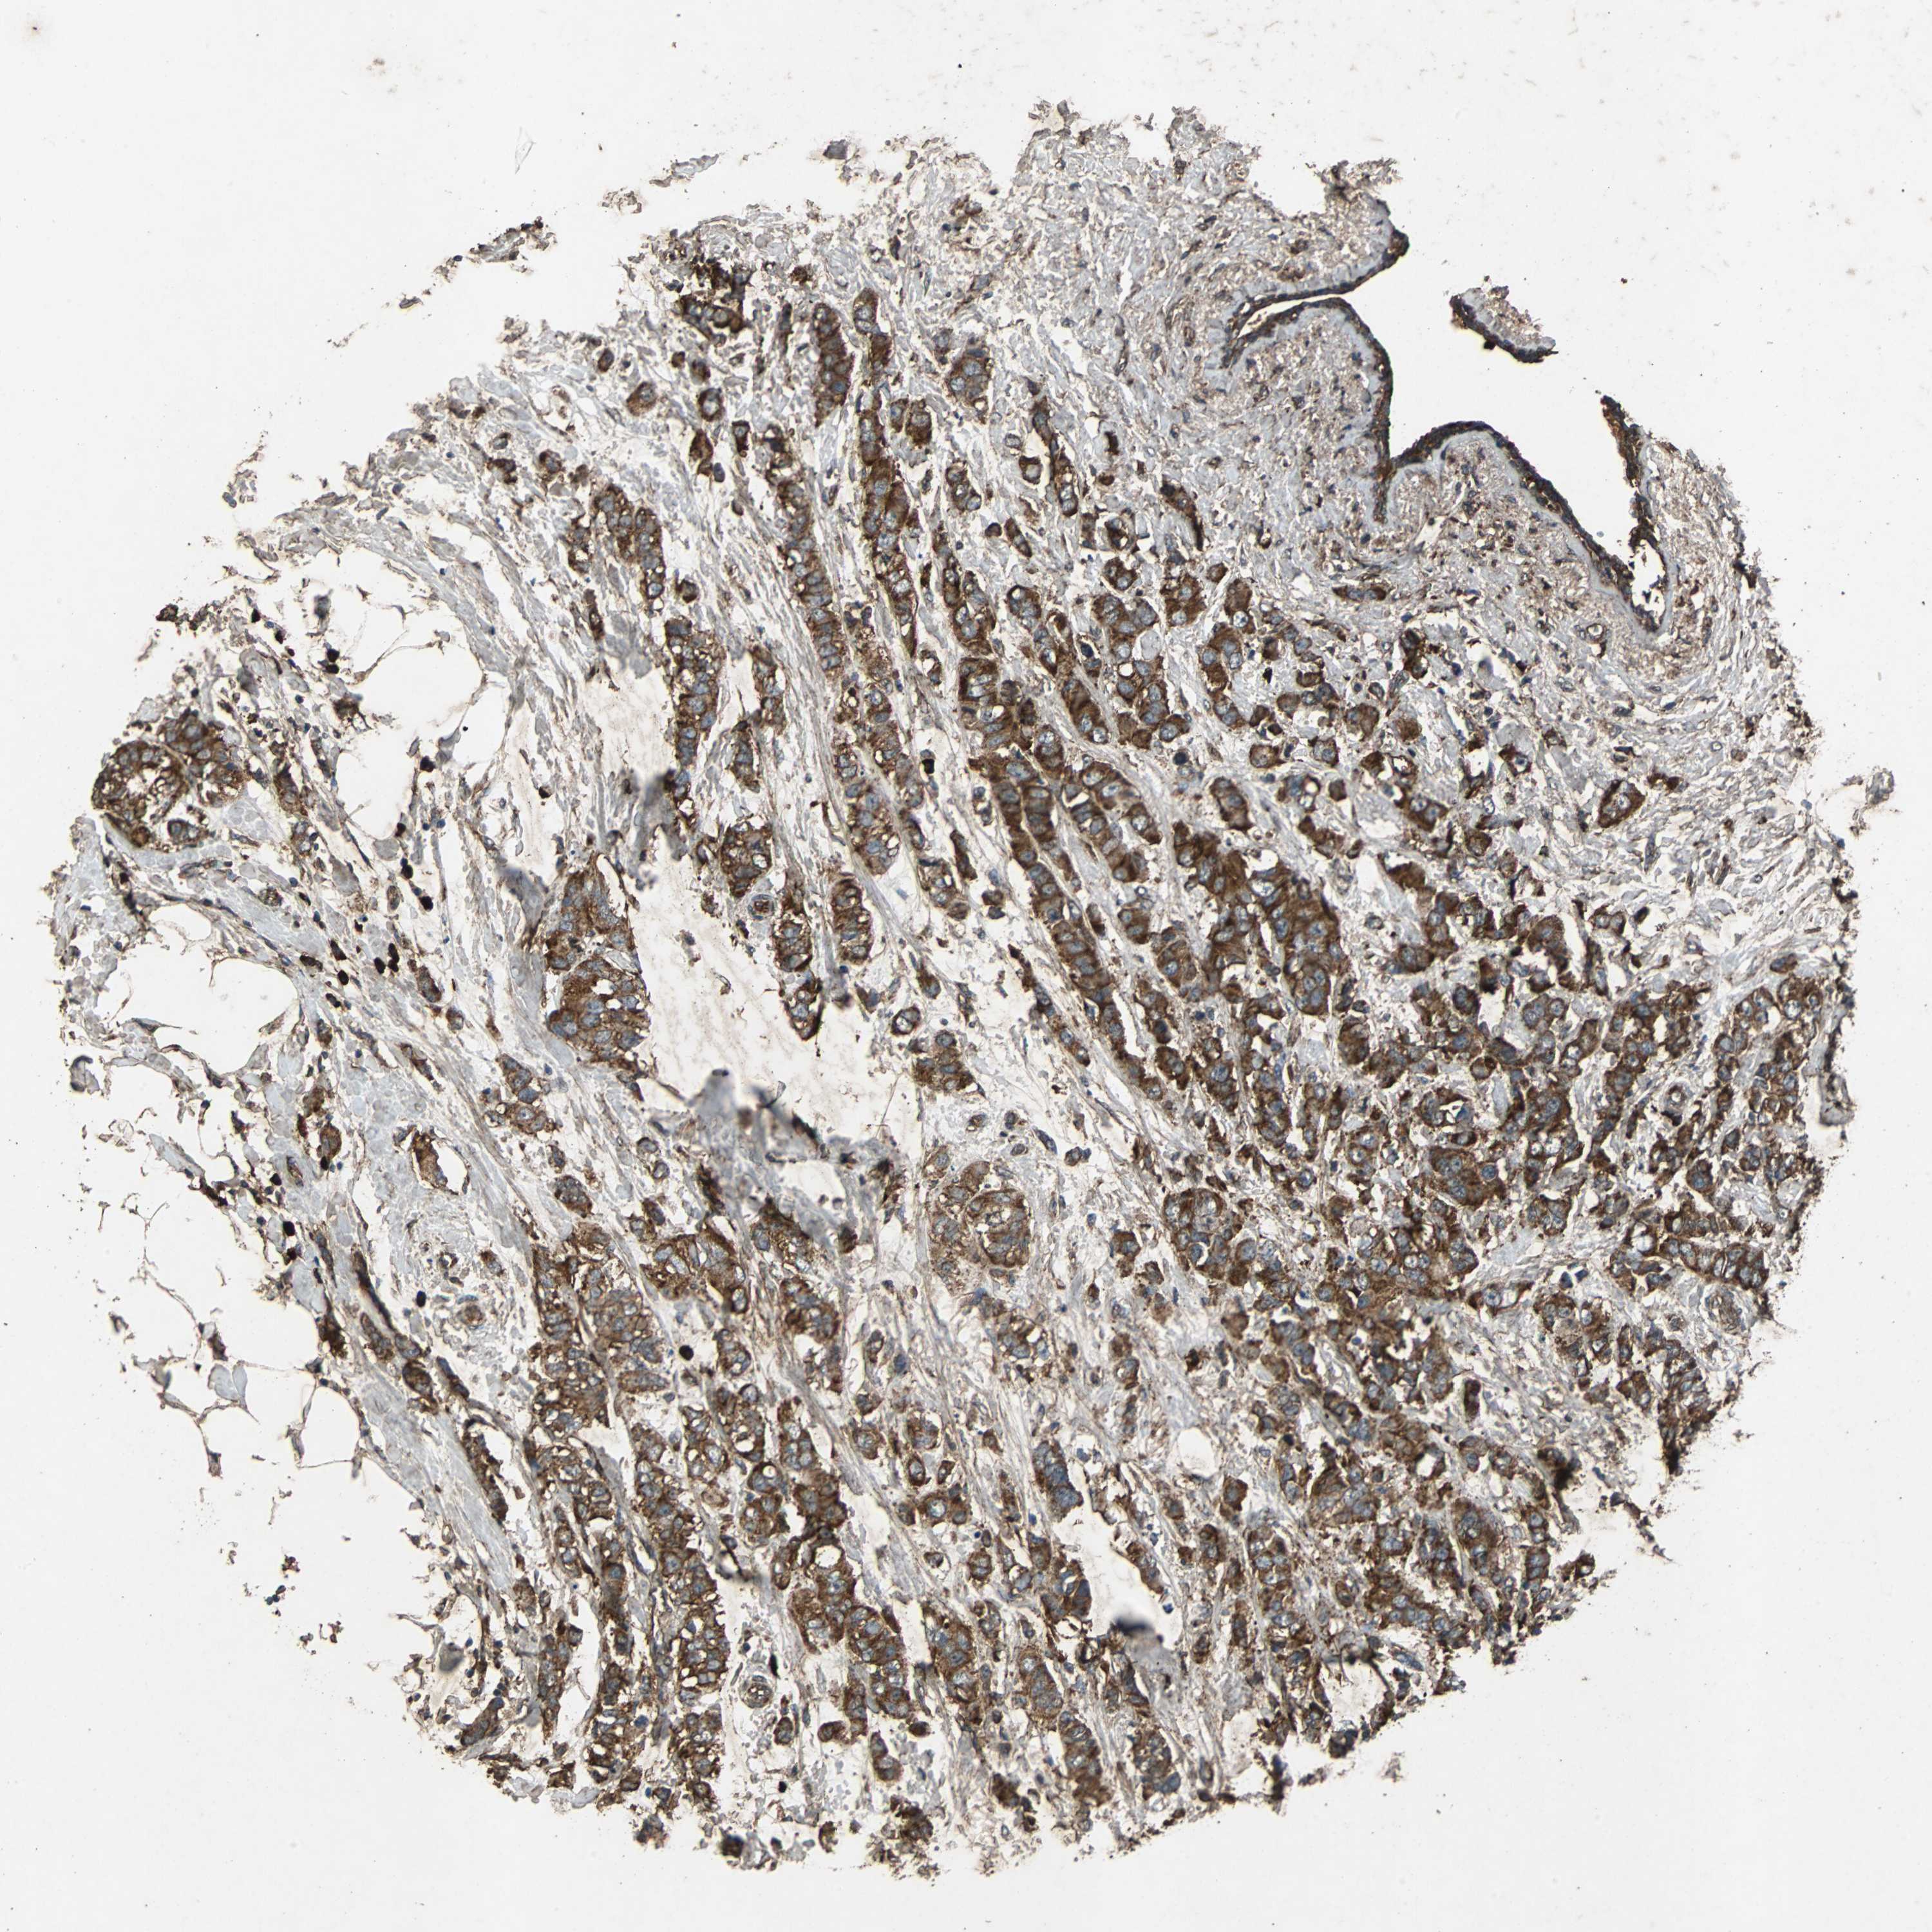

CANCER BREAST CANCER Show tissue menu

BRCA TCGA BRCA VALIDATION PROTEIN EXPRESSION

Breast cancer

Human cancer